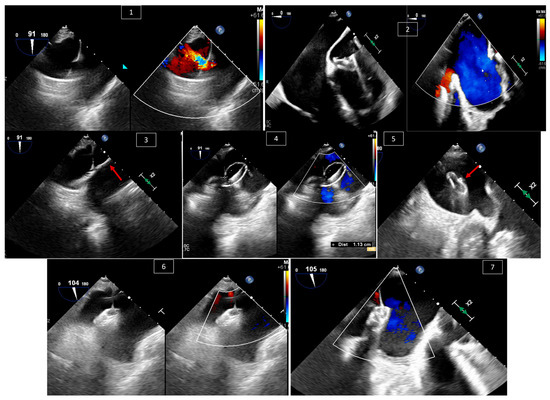

2. Atrial Septal Defect (ASD) and Patent Foramen Ovale (PFO) Closure

3. Ventricular Septal Defect (VSD) Closure

4. Transcatheter Edge-to-Edge Repair (TEER) of Systemic AV Valve

5. Paravalvular Leak Intervention

6. Baffle Complications in Atrial Switch Operations

7. Interventions in Fontan Circulation